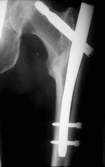

Das Ergebnis ist eine Fehlplazierung der Schenkel- halsschraube Diese korrekte Lage wurde mit dem neuartigen Zielgerät erreicht. Das neue Zielgerät läßt sich leicht auf dem Obturator befestigen und zielt sowohl in der Aufsicht, als auch in der Seitaufnahme. Links ist die falsche Position und rechts durch Drehung des Zielgerätes die korrekte Position zu sehen. Liegen die drei Drähte nun zu weit Proximal, muß der Nagel wieter nach distal geschoben werden.

Position des Gerätes in seitlicher Lage ergibt beim Röntgen die folgenden Aufnahmen. Der geriffelte Draht liegt nicht zwischen den zwei glatten Drähten. Bewegen des Zielgerätes ergibt das erforderliche Bild. Sollten die so positionierten Drähte sich nicht über dem Kopf abbilden, muß der Nagel gedreht werden. Auf diese Weise erreicht man die korrekte Lage der Schenkelhalsschraube in die Mitte des Kopfes, ein Auswandern der Schraube ist so unmöglich.